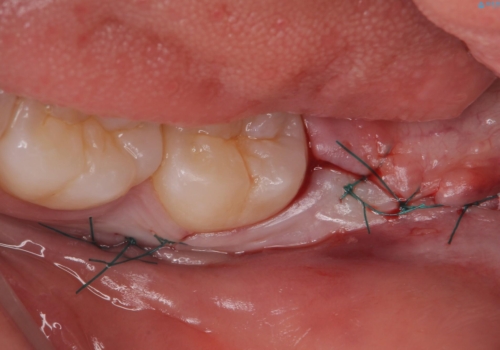

左側の親知らずを上下同時に抜いていきます。

時間は約60分で施術しました。

また術後丁寧に縫合をすることで治癒後の歯茎の状態もきれいにすることができます。